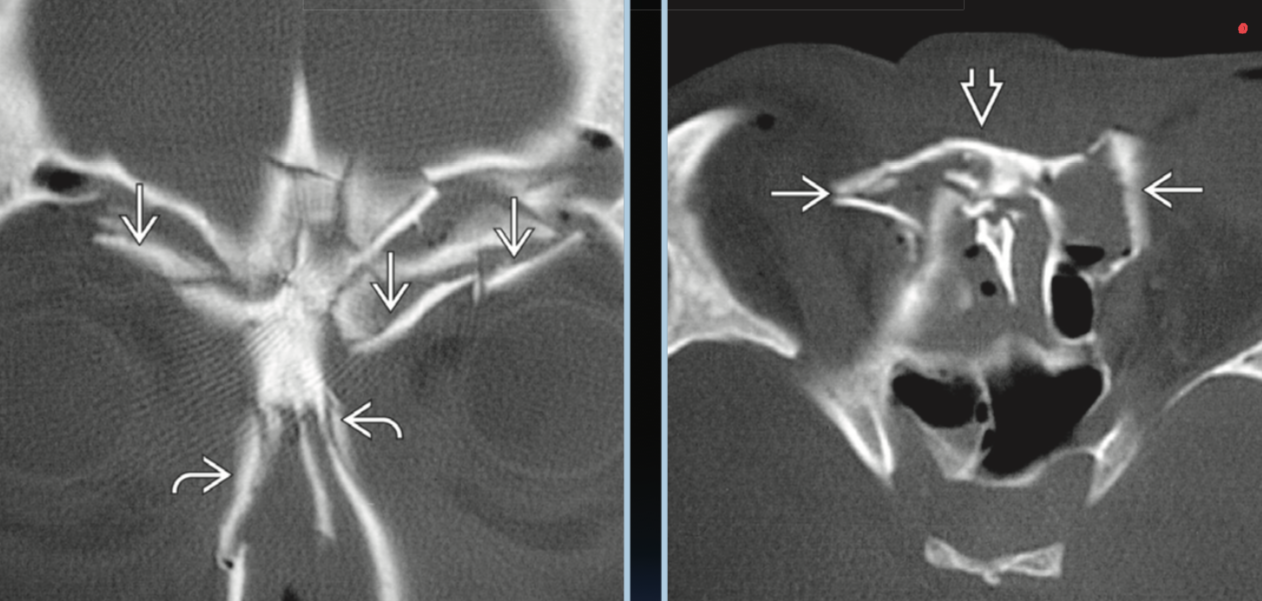

Naso-orbito-ethmoidal fracture. What to report on CT?

Naso-orbital-etmoidal fractures complications?